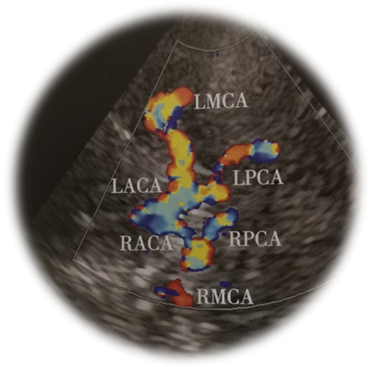

TCD检查可以观察颅内主要11根动脉血管(双侧颈内动脉终末段、大脑中动脉、大脑前动脉、大脑后动脉、椎动脉及基底动脉)的流速和频谱形态,评估根据流速和频谱形态评估颅内动脉有无狭窄、闭塞等情况。TCD是盲探,由检查者通过部位、深度和方向对血管进行定位,且TCD取样容积大,会出现偏差,另外由于两种检查分别进行,相互不知道对方检查的结果,没有整体分析,容易造成误诊及漏诊,比如颅内段椎动脉有切迹,是锁骨下动脉盗血还是椎动脉狭窄就需要结合颈动脉超声了。

TCCD在TCD成像基础上,加入二维灰阶成像及彩色多普勒血流成像可直观地识别颅内结构,尤其可以观察帕金森病黑质有无高回声及其范围,第三脑室及侧脑室前角的宽度、中脑、丘脑结构、脑内重要核团如中缝核、红核回声,更准确的定位颅内血管,通过角度校正,可更为准确地取得狭窄处,狭窄前、狭窄后血管腔的实时血流动力学信息。定位及定性更加准确、全面,对侧枝循环的评估更加精确。